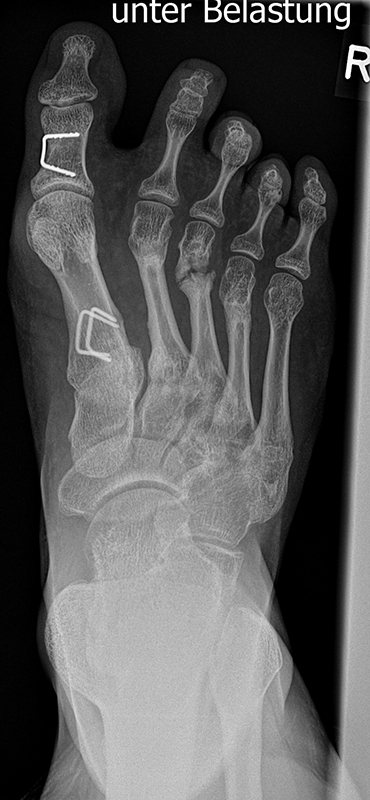

Abb. 2 a-c: offene Wachstumsfugen MT I Basis und Zehen (a), teilweise geöffnete Wachstumsfugen (b) und geschlossene Wachstumsfugen (c).

Zum Lesen der Bildbeschreibung und zur Vollansicht bitte die Bilder anklicken. Bilder: A. Helmers.